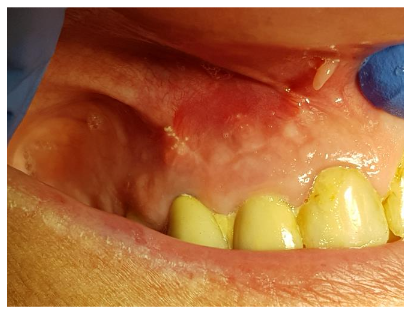

First clinical symptom was a vestibular abscess

Four days post abscess incision

No possibilities to endodontic treatment at all

After flap opening the structure of the cyst is visible